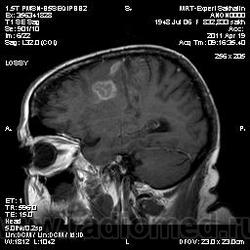

Постконтрастные сканы есть.После надписи"постконтраст".

При просмотре исседования на постконтрастных сканах выскакивает надпись "Омнискан"-сама недавно заметила.

А контраста много не бывает. 10 мл - в зависимости от веса. В данном случае вижу слабо законтрастированное сосудистое русло. Либо поздно.

Как вариант хочу предложить на рассмотрение грибковое поражения головного мозга или токсоплазмоз. В таком случае полностью укладывается изменение сигнальных характеристик и на нативе и на постконтрастных сканах. Можно проверить на иммуносупресивные состояния, на наличие грибкового эндокардита (Узи сердца).

На опухоль не тянет. Для инфаркта и банальной гемморрагии не характерен тип накопления контраста на мой взгляд.

Исследование в динамике-сама сегодня случайно узнала. что была, но не в мою смену.

На динамике видно что это был действительно ОНМК - сомнений нет, данных за объем не вижу.

Ребята, если это ОНМК, то "головной болью" тут никак не обойтись. С таким инсультом быстренько попадают в неврологию.